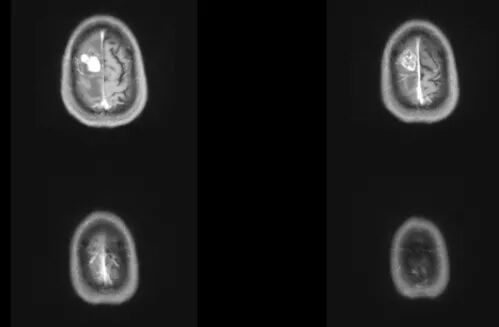

25歲的小麗(化名)近四年來一直存在月經(jīng)不調(diào)的情況,有時延期,甚至停經(jīng),近日來還出現(xiàn)泌乳的情況。她先后在多家醫(yī)院婦科、內(nèi)分泌科就診,但“月經(jīng)不調(diào)”癥狀不見好轉(zhuǎn)。醫(yī)生建議查血激素水平和垂體磁共振后,結(jié)果發(fā)現(xiàn)“月經(jīng)不調(diào)、泌乳”竟是顱內(nèi)垂體瘤導致。還好經(jīng)過內(nèi)鏡下微創(chuàng)手術(shù)治療,小麗最終康復出院。

垂體瘤